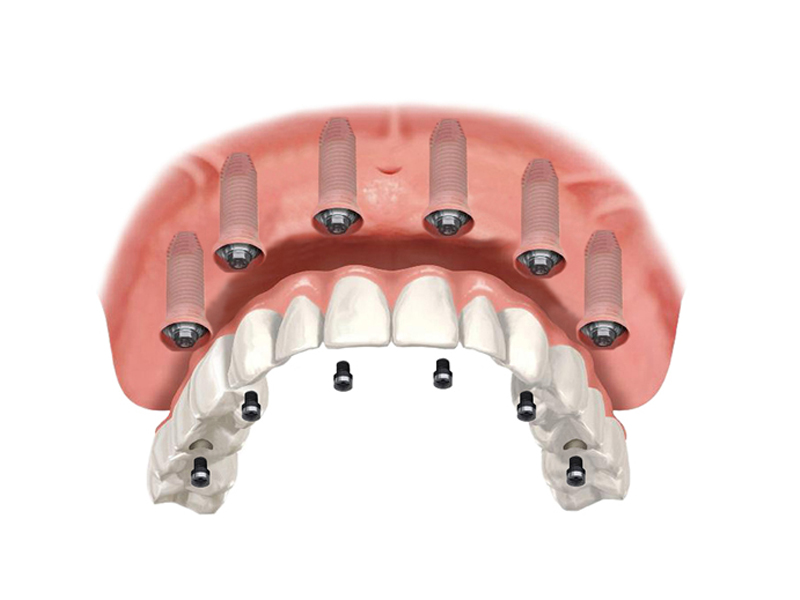

Implantology All on 6

The newAll on Six implant (All on 6) technique could be right for you if you already have a denture or a skeleton and you need to extract the last remaining teeth

• This solution is ideal if you want to have fixed teeth quickly, easily and without painful bone grafting;

• This technique can also be applied for those who are edentulous (toothless) for a long time;

• This operation is carried out after the panoramic and CT scan of the patient's dental arches;

• If there are certain conditions, the intervention can be performed with the transmucosal technique (at the discretion of the doctor).

Another great advantage that derives from the All on 6 method is the immediate load, on the inserted implants your new fixed teeth are fixed in the same session or at most in a second sitting after a few days.

Thanks to immediate loading, if there are certain conditions, it is no longer necessary to wait months before chewing on new teeth!